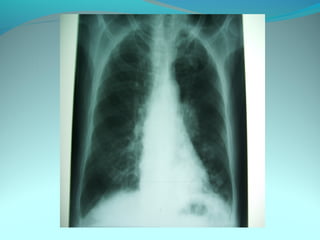

Cliché normal